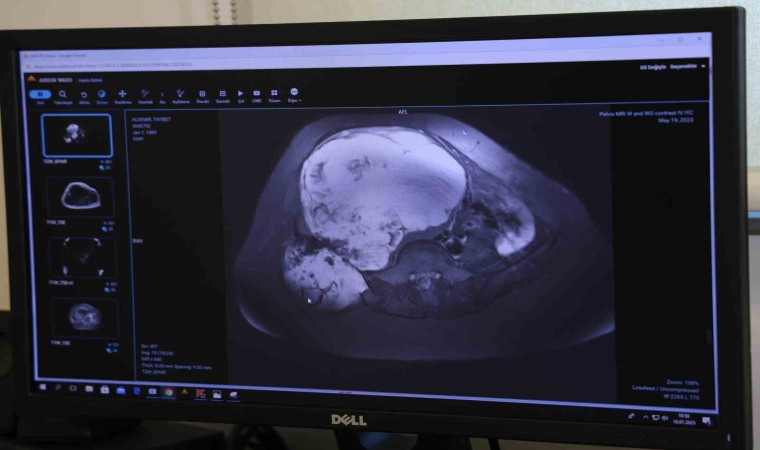

Burada Ortopedi ve Travmatoloji Kliniği’nde görevli Prof. Dr. Ahmet Kapukaya’ya başvuran Aldemir, yapılan tetkikler sonucu doktorunun da yönlendirmesiyle ameliyat olmaya karar verdi. Türkiye’de nadir yapılan ve 6 saat süren ‘Pelvik rezeksiyon’ ameliyatıyla genç kadının leğen kemiğindeki tümör temizlendi.

İhlas Haber Ajansı’na konuşan Ortopedi ve Travmatoloji Uzmanı Prof. Dr. Ahmet Kapukaya, “Hastamız bize geldiğinde tümörü çok ilerlemişti. Ameliyat olması halinde yüzde 98 bacak kaybı, yüzde 95’de ölüm riski var denilmişti. Ancak Adana Şehir Eğitim ve Araştırma Hastanemizin alt yapısı bu tür ameliyatları yapmaya çok müsait. Bizde hastamıza riskleri anlattık ve ekip halinde bu ameliyatı gerçekleştirdik. Leğen kemiğini bölgeden çıkarttık, tümörü temizledik ve vücuttan alınan diğer kemiklerle o bölgede yeni bir leğen kemiği oluşması için kaynamaya bıraktık” diye konuştu.